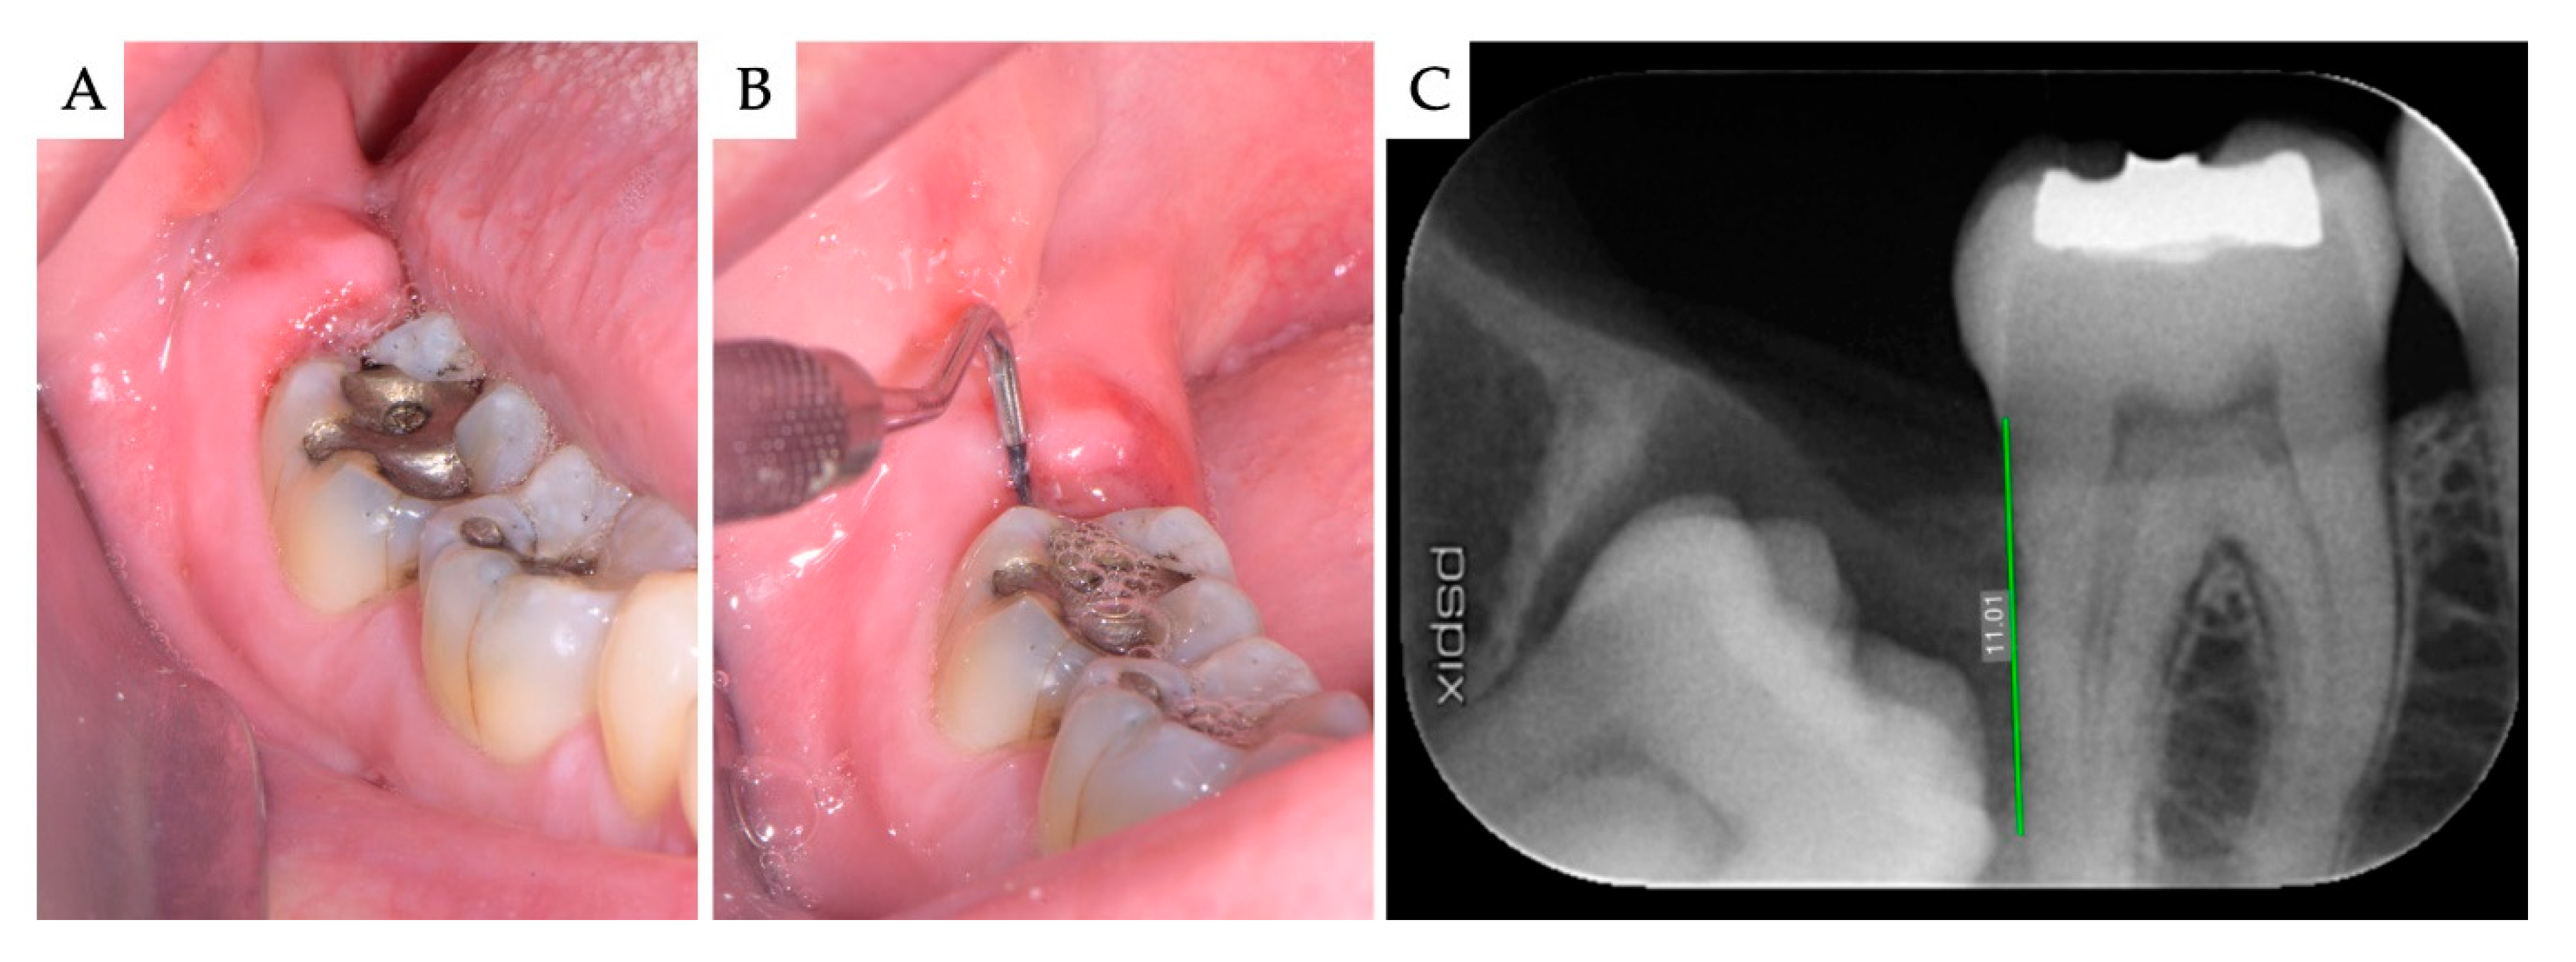

3. Results